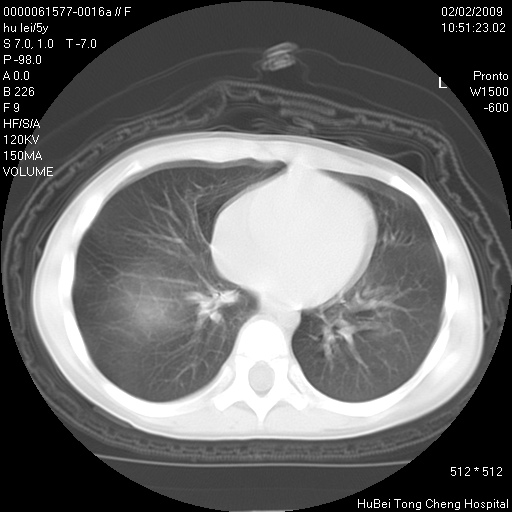

标题: PED1732:M5Y,右肺囊性占位!

患者:男,5。无明显不适,拍胸片考虑右肺囊肿。

行ct扫描,图象如下:

右肺巨大囊肿或包虫

考虑先天性巨大支气管肺囊肿,建议包虫实验除外肺包虫。

右肺巨大囊性占位性病变;考虑巨大肺囊肿,不排除淋巴管瘤可能。